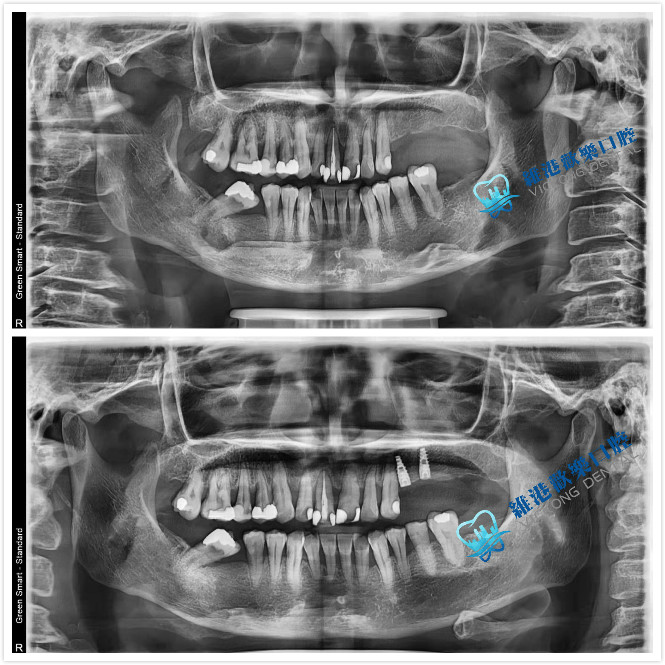

案例分享:

拔除阻生智慧齒:阻生智慧齒周圍的牙齦常常會發炎,疼痛,嚴重時臉頰可以腫脹,張口困難,甚至全身發熱,頜下淋巴結腫大。阻生牙常常還會引起鄰牙齲壞,鬆動,牙槽骨吸收等症狀。